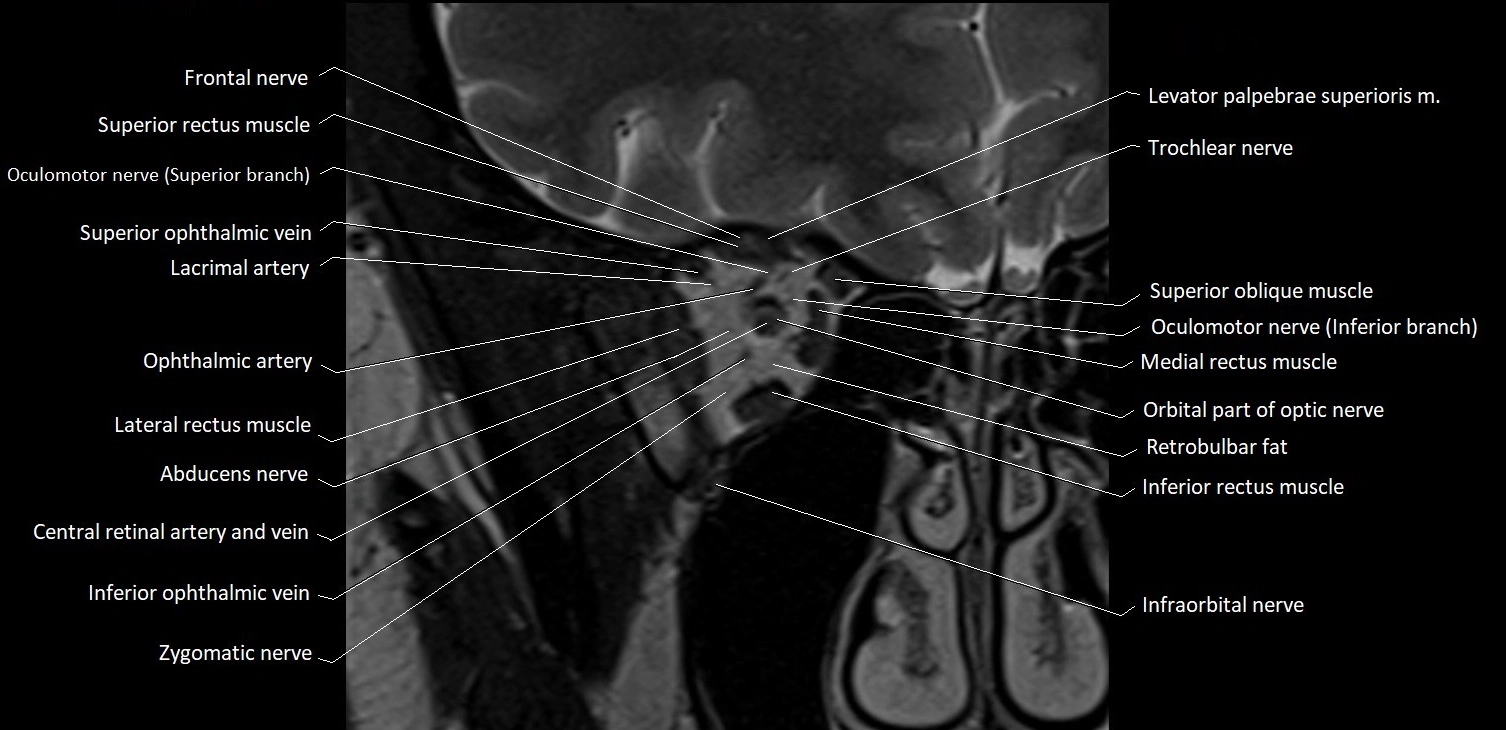

MRI images